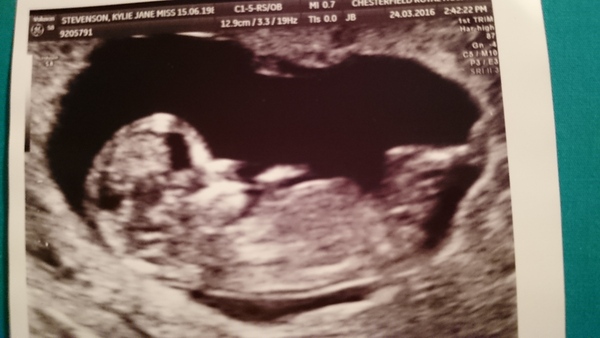

Had my 12 week official scan today and they agreed with the dates for my private scan so I'm 13+4 today; almost at the 2nd trimester! My baby girl was lying there chilled out legs crossed and hands behind her head at one stage. I'm completely in love with her already.

wow, thats a great photo Cake! congrats, she looks perfect already :-)

Ah wow, that's an amazing photo! I love how she is chilled out Smile

That's a lovely picture Cake :-)

Great pic cake!!

Lovely scan cake!

Great pic cake!

Had my dating scan today. Put my due date back a few days so now due 5th October. Saw a lovely wriggly baby in there Grin

Aaaah gorgeous scan pictures Cake and fish! So exciting!